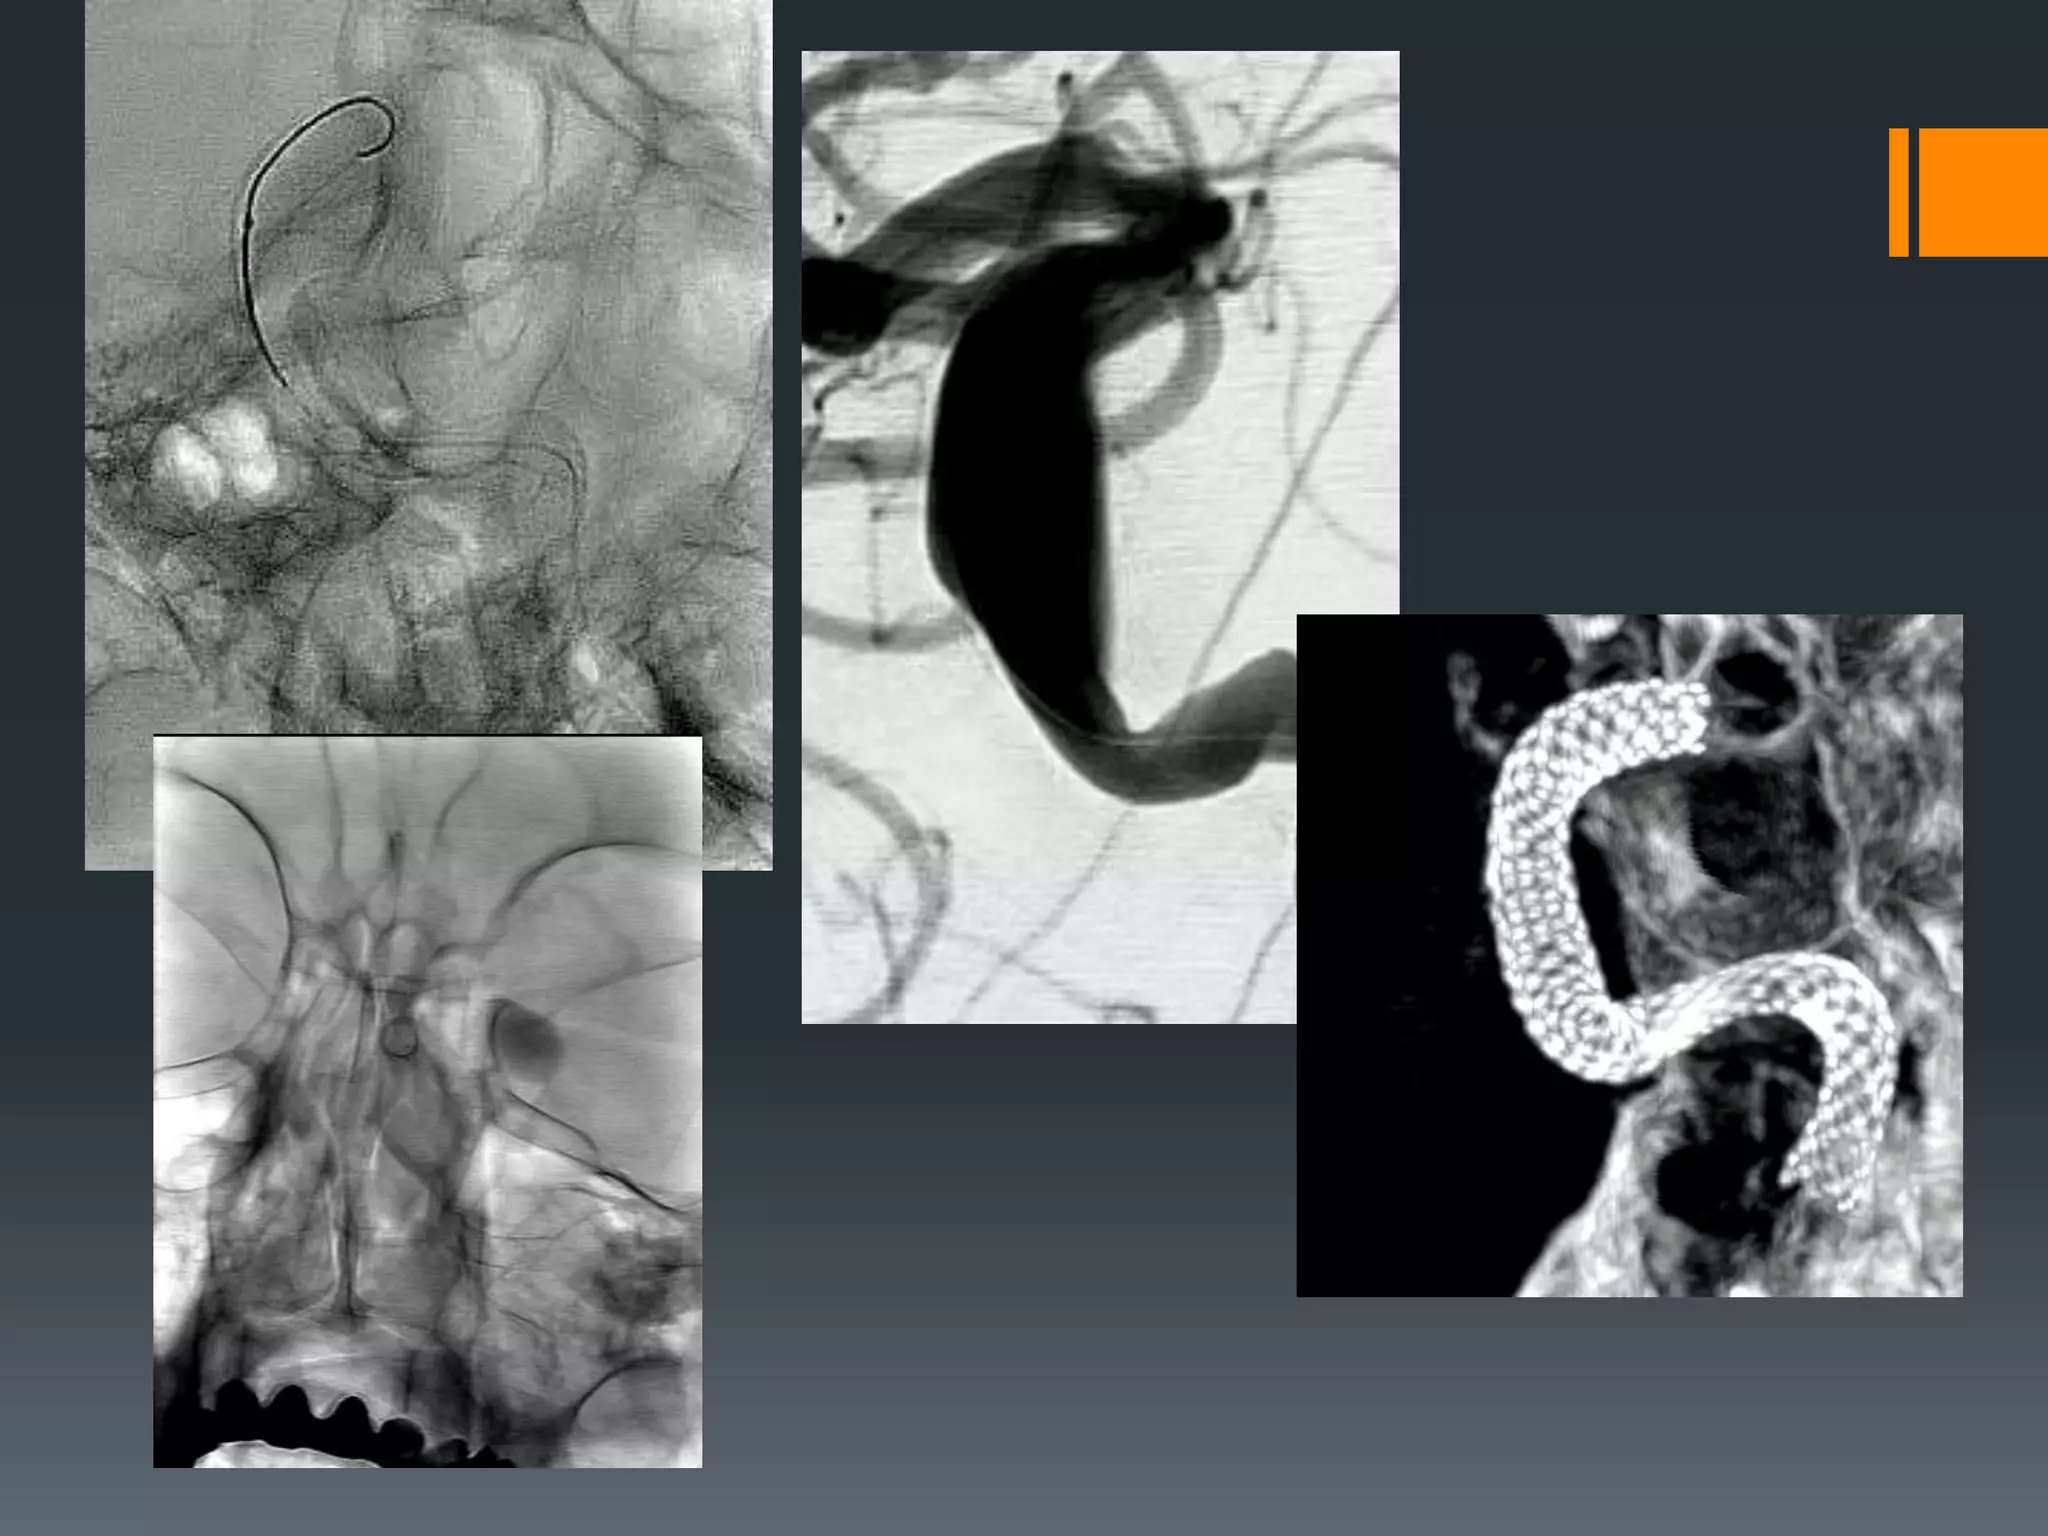

This document discusses tricks and techniques for difficult cannulations during neurointerventional procedures. It outlines strategies for accessing the aortic arch, internal carotid artery (ICA), and areas distal to aneurysms. Long sheaths, distal access catheters, and co-axial techniques are presented as options that have improved cannulation success. Guidance on sheath and catheter selection is provided for different vessel paths. The importance of catheter placement as high as possible in the ICA is emphasized. Reverse curve cannulations are also mentioned. Overall, the document stresses that careful cannulation is critical for procedural success and different strategies may be needed depending on the vessel target.